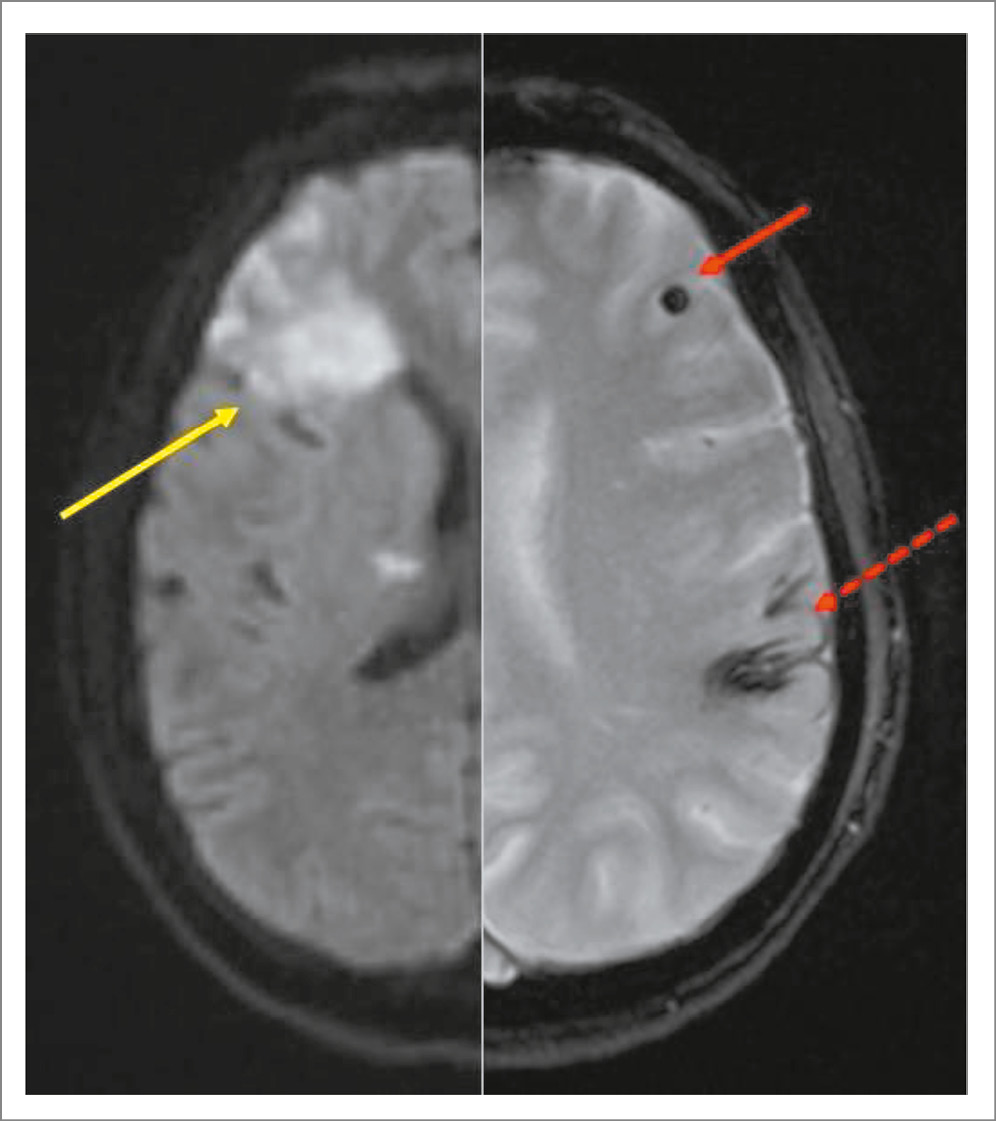

Нейровизуализационные данные представлены в табл. 2. У пациентов с ИЭ очаги ИИ соответствовали основным характеристикам кардиоэмболии: поражение разных сосудистых бассейнов (84%), множественные (>1 зоны) инфаркты (88%), кортикально-субкортикальная локализация (100%; глубинная/стволовая – у 32%), высокая частота геморрагической трансформации (44%). У 28% пациентов максимальный размер инфаркта составил >5 см, у 20% − от 2 до 5 см, у 52% − <2 см. ЦМК выявлены в 64% случаев, при этом в 93,8% локализация ЦМК долевая, а у 56% пациентов с ЦМК наблюдались множественные (>1) микрокровоизлияния. САК выявлено у 28% пациентов (при этом из 7 пациентов инфекционная аневризма по данным магнитно-резонансной ангиографии выявлена только в 1 случае, а сосуществующие ЦМК – у 6). Изучаемый нами паттерн сочетания кортикально-субкортикального инфаркта с долевым ЦМК или САК (рис. 1) наблюдался у 64% пациентов в группе ИЭ, в контрольной – у 12%. ОШ для наличия ИЭ составило 13,0 (95% доверительный интервал 3,04–55,9; p<0,001). Точность признака – 76%, специфичность – 71%, чувствительность – 84%.

Рис. 1. Паттерн сочетания кортикально-субкортикального инфаркта (желтая стрелка указывает на острые ишемические изменения на МРТ-DWI) и ЦМК (сплошная красная стрелка) или САК (пунктирная красная стрелка).